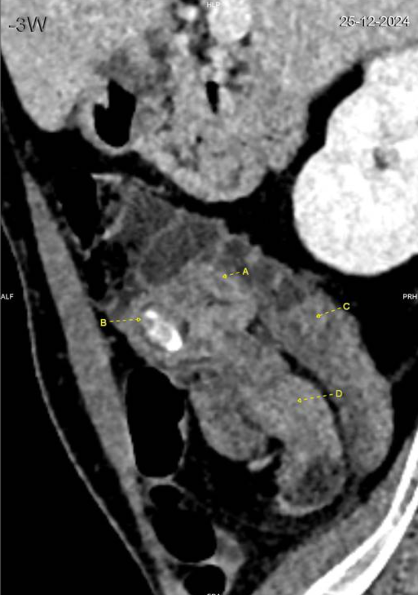

Le CT scanner abdominal montre une invagination iléo-cæcale sur environ 8 cm, sans signe de souffrance intestinale (absence de pneumatose pariétale ou de liquide libre). La valve iléo-cæcale présente un épaississement circonférentiel discrètement irrégulier, accompagné d’une calcification de 17 mm (stercolithe). L’appendice est non distendu, et aucune adénomégalie suspecte n’est observée.

Coupe transverse